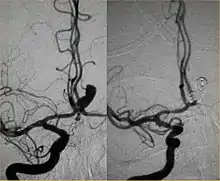

Parallel to the development of catheters, in the radiology and neuroradiology units, image technology dramatically improved: Charles Mistretta in 1979 invented digital subtraction angiography (DSA), the technique currently in use. It consists of performing skull radiography under basic conditions which are then "subtracted" to the image after contrast media injection, to provide an image where only brain vessels are displayed, with great improvement in the diagnostic potential.

Between the end of the 1980s and the beginning of the '90s, INR was suddenly revolutionized after the work of two Italian physicians: Cesare Gianturco and Guido Guglielmi. The first combined a deep knowledge of diagnostic radiology with a great ability to solve technical and manual problems. He invented Gianturco's coils, which he used to make the first attempts to embolize arteries and aneurysms.[8] Gianturco also patented the first endovascular stent approved by the American FDA;[8] a device with a great legacy. In the second half of the 1980s, Sadek Hilal was the first in Columbia University to use coils to treat brain aneurysms; but this technique was inaccurate and dangerous because the coils were released with little control with great risk of occluding the vessel from which the aneurysm originated (parent vessel).[9] The coil embolization was revolutionized by the work of Guido Guglielmi in UCLA, who realized that electricity could function as a controlled release mechanism for coils; in 1991 he published two works dealing with the embolization of brain aneurysms by means of detachable platinum coils[10] (Guglielmi's coils). The treatment of aneurysms was thus made more accessible and safe.